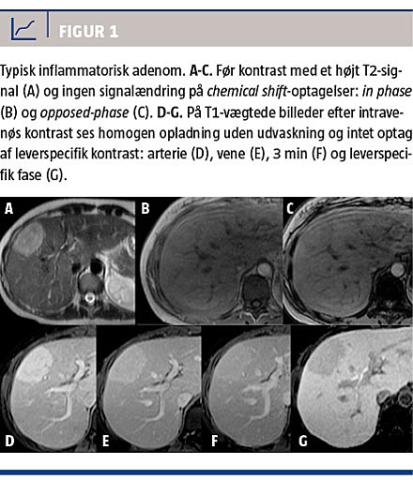

Adenomer med muteret HNF1α-gen (Figur 2) er

iso- eller lethyperintense på T2-vægtede billeder og iso- eller hyperintense på T1-vægtede billeder med diffust signaltab på chemical shift-optagelser pga. intracellulær steatose. De ses ofte i en diffust steatotisk lever og har moderat opladning i arteriefase, ingen persisterende opladning i senere faser, men vender hurtigt tilbage til udseendet før kontrastindgift [12, 22].

β-cateninaktiverede og uklassificerbare adenomer har ikke et specifikt udseende på en MR-skanning, men de indeholder ikke fedt, har oftest kraftig arteriel opladning med eller uden udvaskning og kan ligne HCC [22]. Vha. MR-skanning kan man således skelne de fedtholdige adenomer med muteret HNF1α-gen fra de øvrige typer. Fælles for alle adenomtyper er, at de i modsætning til FNH ikke indeholder galdeveje og derfor ikke optager hepatobiliær, leverspecifik MR-kontrast. Det gælder både for gadobenatdimeglumin, som er et gadoliniumkelat, hvor 5% af kontrasten optages i levercellerne og udskilles i galdevejene 1-3 timer efter indgift [23], og for gadoxetat, hvor op til 50% af kontrasten optages i levercellerne og udskilles i galdevejene efter 15 minutter [24].